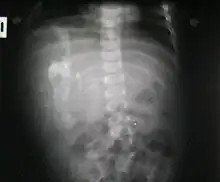

Fetus in fetu (or foetus in foetu) is a rare developmental abnormality in which a mass of tissue resembling a fetus forms inside the body of its twin. An early example of the phenomenon was described in 1808 by George William Young.[1]

There are two hypotheses for the origin of a "fetus in fetu". One hypothesis is that the mass begins as a normal fetus but becomes enveloped inside its twin.[2] The other hypothesis is that the mass is a highly developed teratoma. "Fetus in fetu" is estimated to occur in 1 in 500,000 live births.[3]

Fetus in fetu may be a parasitic twin fetus growing within its host twin. Very early in a monozygotic twin pregnancy, in which both fetuses share a common placenta, one fetus wraps around and envelops the other. The enveloped twin becomes a parasite, in that its survival depends on the survival of the host twin, by drawing on the host twin's blood supply. The parasitic twin is anencephalic (without a brain) and lacks some internal organs, and as such is unable to survive on its own. As the host twin has to "feed" the enveloped twin from the nutrients received over a single umbilical cord, they usually die before birth.